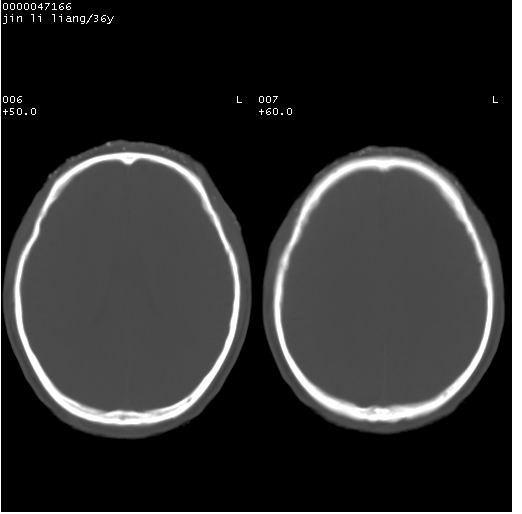

患者 男,36岁。头面部“土炮”炸伤。pe:面目全非,伤口流血不止。

临床诊断:头面部外伤。

颅脑ct轴位平扫(层厚、层距均为10mm),图像如下:

左眼球内容物浑浊其内见气体影,头面部异物.

左眼球破裂并异物,眶周、额顶部头皮及软组织挫伤并异物

迎面一炮,满脸开曝。额顶部头皮及软组织挫伤并异物,左眼球破裂积气并异物,典型的面目全非,惨不忍睹。

左眼球破裂积气并异物,眶周、额顶部头皮及软组织挫伤并异物,右侧眼环前内分异物

1左侧眼球破裂并积气,球内、框内异物。

2额部顶部软组织伤。